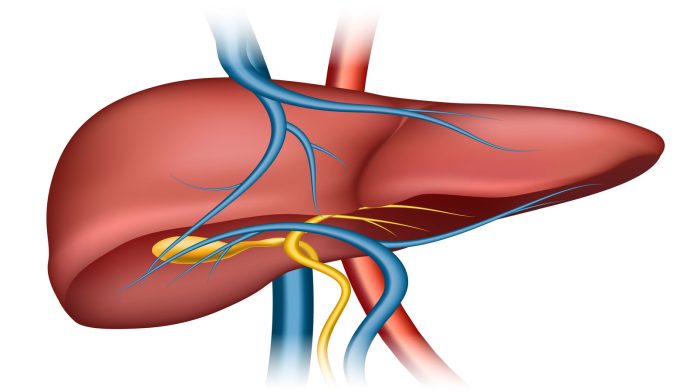

Siroz, karaciğerde meydana gelen kronik ve ilerleyici bir hastalık türüdür. Normal, sağlıklı karaciğer dokusu git gide zarar görür ve yerine skar (fibroz) doku oluşur. Bu skar doku, karaciğerin normal işlevlerini yerine getirmesini engeller. Siroz, karaciğerdeki bu yaygın ve kalıcı hasarın sonucunda ortaya çıkar.

Siroz, genellikle kronik alkol kullanımı, hepatit B veya C enfeksiyonları, yağlı karaciğer hastalığı karaciğer yağlanması ve bazı genetik bozukluklar gibi faktörlerle ilişkilendirilir. Ancak, bazen nedeni bulunmayan kriptojenik siroz denilen durumlarda yaşanabilmektedir. Bu hastalık ciddi bir durumdur ve tedavi gerektirir. Erken teşhis ve uygun tedavi ile sirozun ilerlemesi yavaşlatılabilir ve komplikasyon riski azaltılabilir.